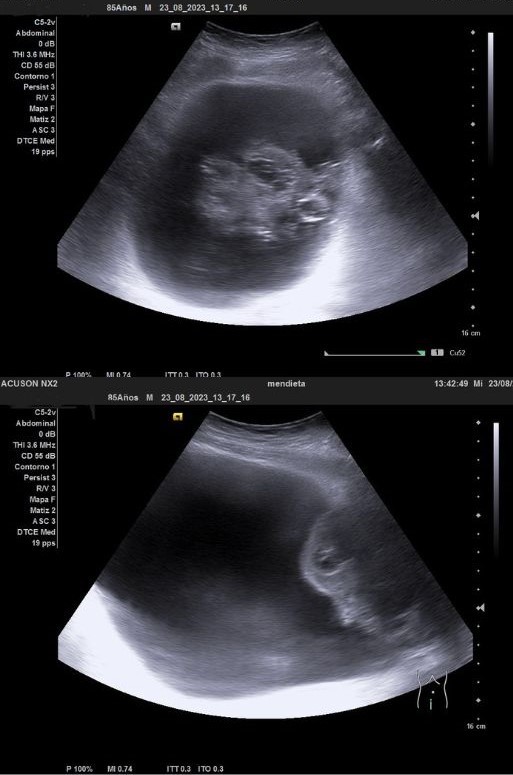

Ecografía venosa: venas femorales y poplíteas permeables. A nivel inguinal se observa imagen heterogénea, mal definida, sospechosa de malignidad.

Ecografía clínica urológica: se objetiva vejiga muy distendida hasta epigastrio con imagen heterogénea en pared posterior de vejiga de gran tamaño que capta al Doppler color sospechosa de malignidad. Con signo de hidronefrosis riñón izquierdo grado III.